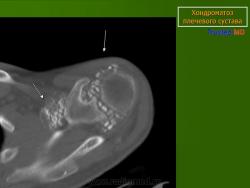

КСС. Хондроматоз внутрисуставной (синовиальный) 1. +

Хондроматоз внутрисуставной (синовиальный).

Хондроматоз

Хондроматоз внутрисуставной (синовиальный)

Хондроматоз суставов — хрящевая островковая метаплазия синовиальной оболочки

Синовиальный хондроматоз

Первичный синовиальный хондроматоз